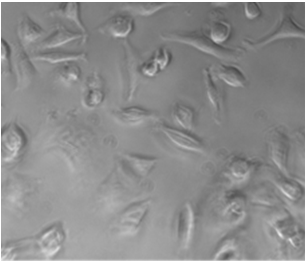

Клетки культивируют в среде ДМЕМ с добавлением 10%-ой инактивированной телячьей эмбриональной сыворотки (FBS), 45 ЕД/мл пенициллина и 45 мг/мл стрептомицина в 5%-ой CO2 среде при 37 °C в CO2-инкубаторе (рисунок 2).

Рисунок 4 - Культура клеток А549